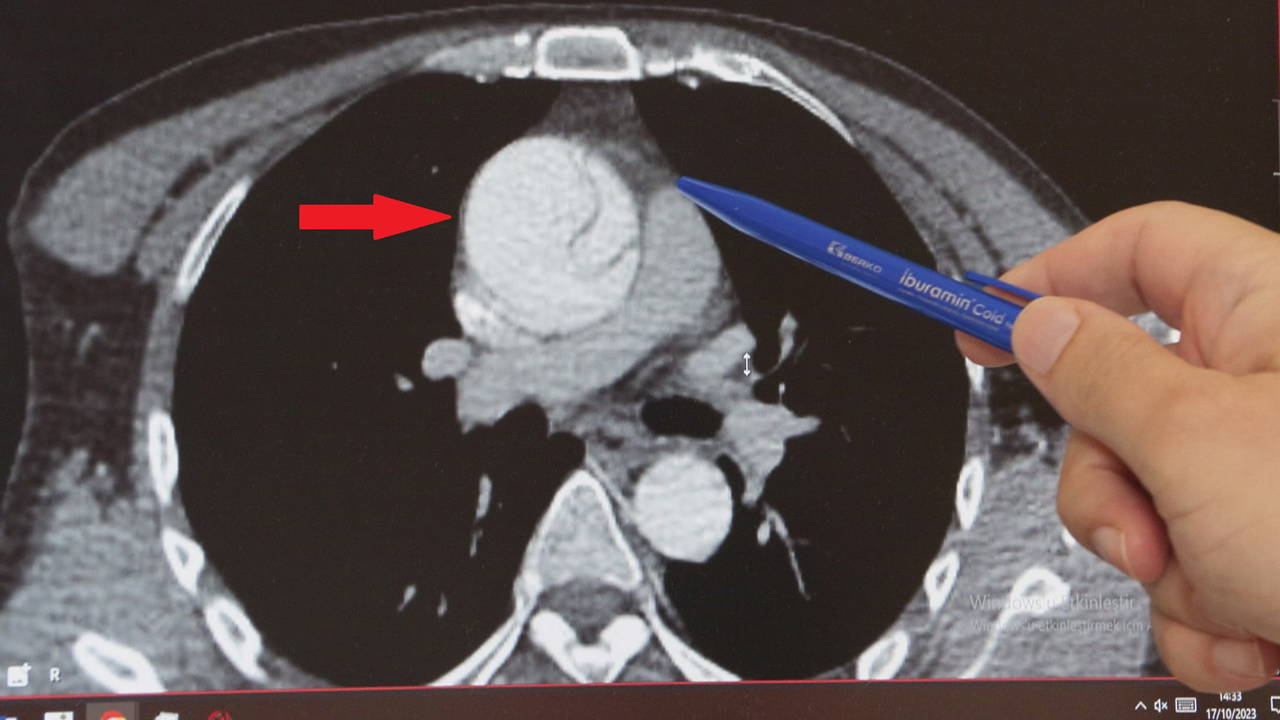

AORT DAMARINDA YIRTIK

Acildeki doktorun şüphelenmesi üzerine tekrar EKO çekildi, abdominal aort anevrizması (AAA) nedeniyle karın bölgesinden geçen aort damarında yırtık olduğu tespit edildi.

Normalde 2 santim çapında olması gereken aort damarı anevrizma (balonlaşma) nedeniyle genişleyerek neredeyse 3 katına ulaşmış, damar duvarında yırtığa neden olmuştu. Hayati riski olduğu anlaşılan Turan, kalp damar cerrahisi ekibi tarafından acilen ameliyata alındı.

Kalp Damar Cerrahisi Klinik Şefi Prof. Dr. Ebuzer Aydın, "Arkadaşlarıyla konuşurken böyle bir boğazında düğümlenme şikayeti oluyor. Bunun üzerine ambulansla acile geliyor. Tetkikleri yapılıyor, daha çok mide şikayetleri düşünülerek o yönde tetkikler yapılıyor ve tedavisi verilip gönderiliyor. Ağrıları geçmeyince tekrar acile geliyor, acildeki doktor arkadaşlarımızın dikkati ve özeni sayesinde ayrıntılı tetkik yapılıyor ve bu sırada aort diseksiyonu olduğu görülüyor. Bize konsülte edildi ve hızlı bir şekilde ameliyathanemizi ayarladık, acilen ameliyata aldık" dedi.